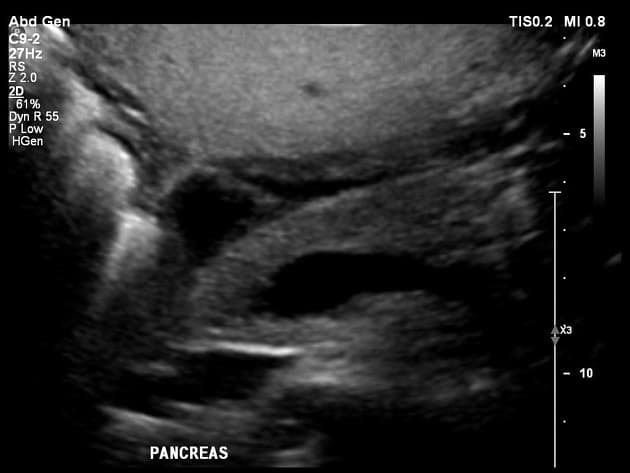

Đường mật không giãn. Tụy, thận, tuyến thượng thận, lách có hình dạng bình thường. Không có dịch tự do hoặc bệnh lý hạch.